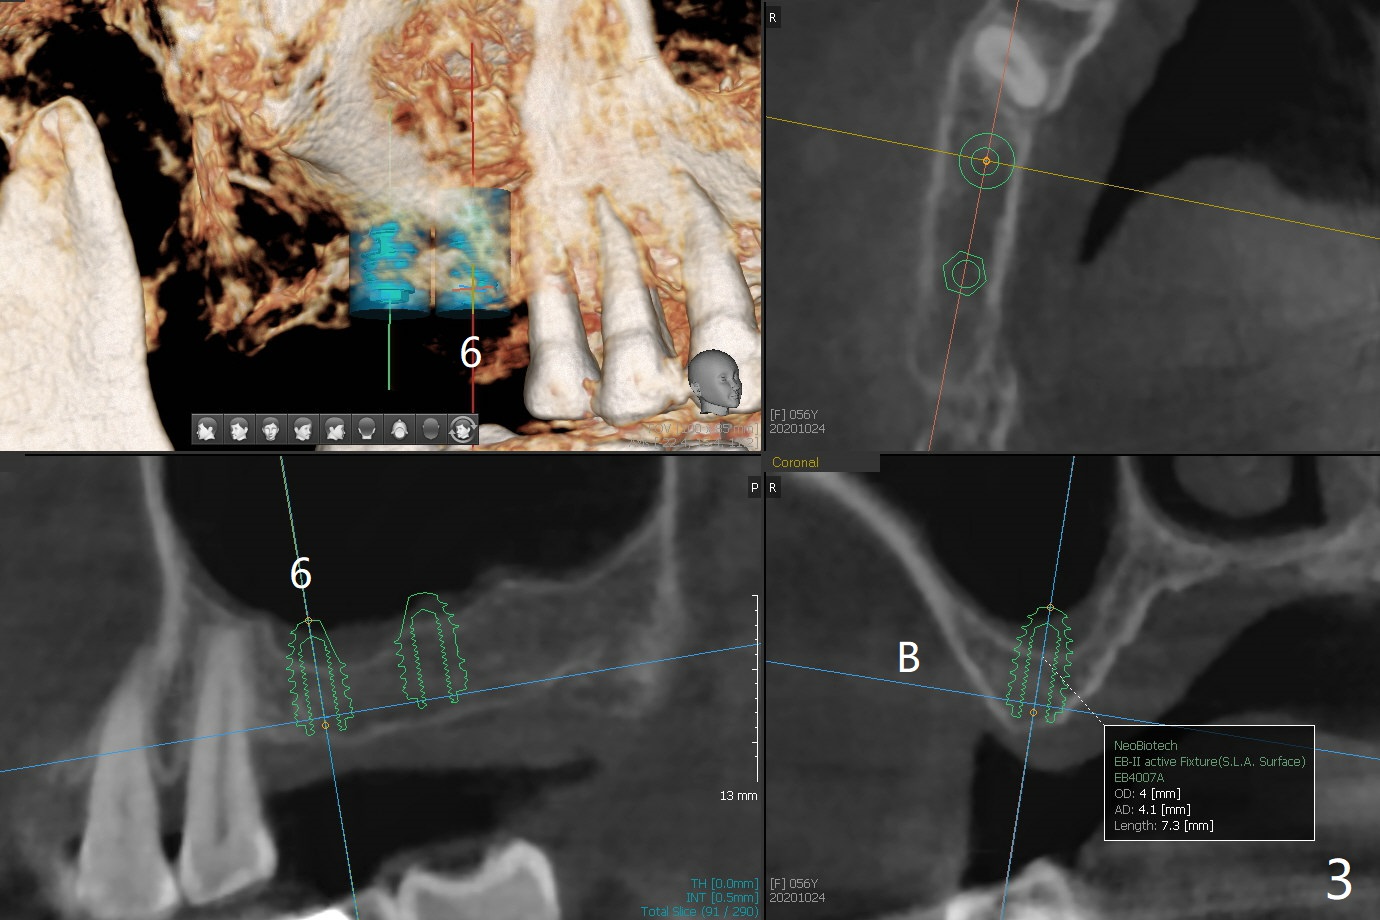

56岁女牙周炎,失去右上6,7以及右下1,后者缺牙间隙特别宽,其余切牙往颊侧移位(flare,病人不愿意拔除,图一)。右上植牙修复后(图二,三),下前牙种植(图四,五(选择窄植体)),建立正常覆盖,同时在邻近切牙唇侧植骨(图七,八:红线)。四-六个月后做局部矫正:使用植牙作为支抗将颊侧移位的前牙(牙冠)往舌侧推移(图七,八:蓝箭头),而牙根可能往唇侧移位(图六:红箭头),所以事先植骨(图七,八:红线)重要。矫正后3-3舌侧放置钢丝树脂固定。Jennifer: #25 implant and crown should be lingualized, as compared to the rest of the lower incisors (flared). After osteointegration, ortho will be conducted to correct the flaring using #25 implant as an anchor.